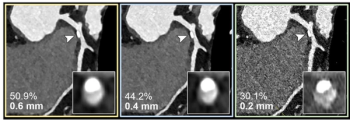

In a comparative study of energy-integrating detector CT myelography versus photon-counting detector CT (PCD-CT) myelography for the detection of cerebrospinal fluid-venous fistulas (CVFs) in cases of spontaneous intracranial hypotension, PCD-CT myelography demonstrated 10 to 19 percent higher sensitivity rates with reviewing radiologists.